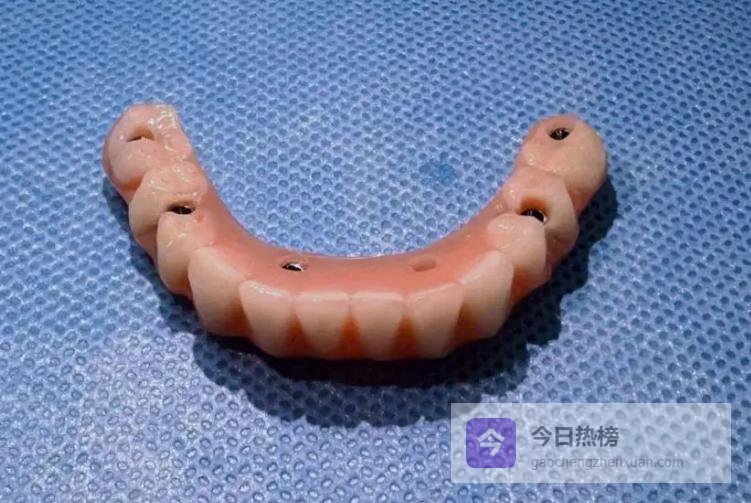

第15条:前牙一定要用定制基台。 尤其是门牙,现成基台做出来的牙齿特别假,美观度极差。多花点钱做定制,笑起来才自然,别人根本看不出是假牙。